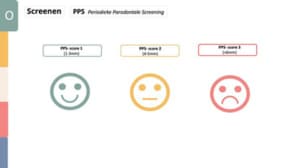

Periodieke parodontale screening (PPS)

De PPS-score kan worden opgedeeld in 3 scores en bijbehorende vragen die het beslissingsmoment vereenvoudigen.

PPS 1 – pocketdiepe 1-3 mm

- Is er sprake van veel plaque,

- Is er sprake van bloeding

- Is er sprake van tandsteen,

- Is er sprake van plaqueretentiefactoren?

- Voldoende mondhygiëne zelfzorg?

– Ja > dan afspraak voor volgende PMO

– Nee > Paro-preventie traject

PPS 2 – pocketdiepte 4-5 mm dan komen erbij:

- Alle afwegingen zoals bij score 1

- Is er sprake van pseudopockets?

- Is er sprake van vergevorderd aanhechtingsverlies?

- Zijn er furcatieproblemen?

- Zijn er risicofactoren met betrekking tot algemene gezondheid?

- Is er sprake van factoren van ongezond gedrag (roken, stress, overgewicht)?

Het advies is om te inventariseren wat de mate van zelfzorg en motivatie is. Daarnaast is voorlichting, begeleiding en advies omtrent gezond gedrag erg belangrijk. Subgingivale reiniging van de pockets van 4-5 mm is ook geïndiceerd. Wanneer er onvoldoende respons is op de behandeling zal aanvullend (parodontaal) onderzoek nodig zijn.

PPS 3 – pocketdiepte >6 mm dan komen erbij:

- Alle afwegingen zoals bij score 2

- Is er sprake van gecombineerde paro-endo problematiek?

- Sprake van geimpacteerd buurelement?

- Fracturen of itrarogene restauratieve behandeling?

Bij een PPS-score van 2 of 3 is het geadviseerd om aanvullend (parodontaal) onderzoek te doen die bestaat uit: